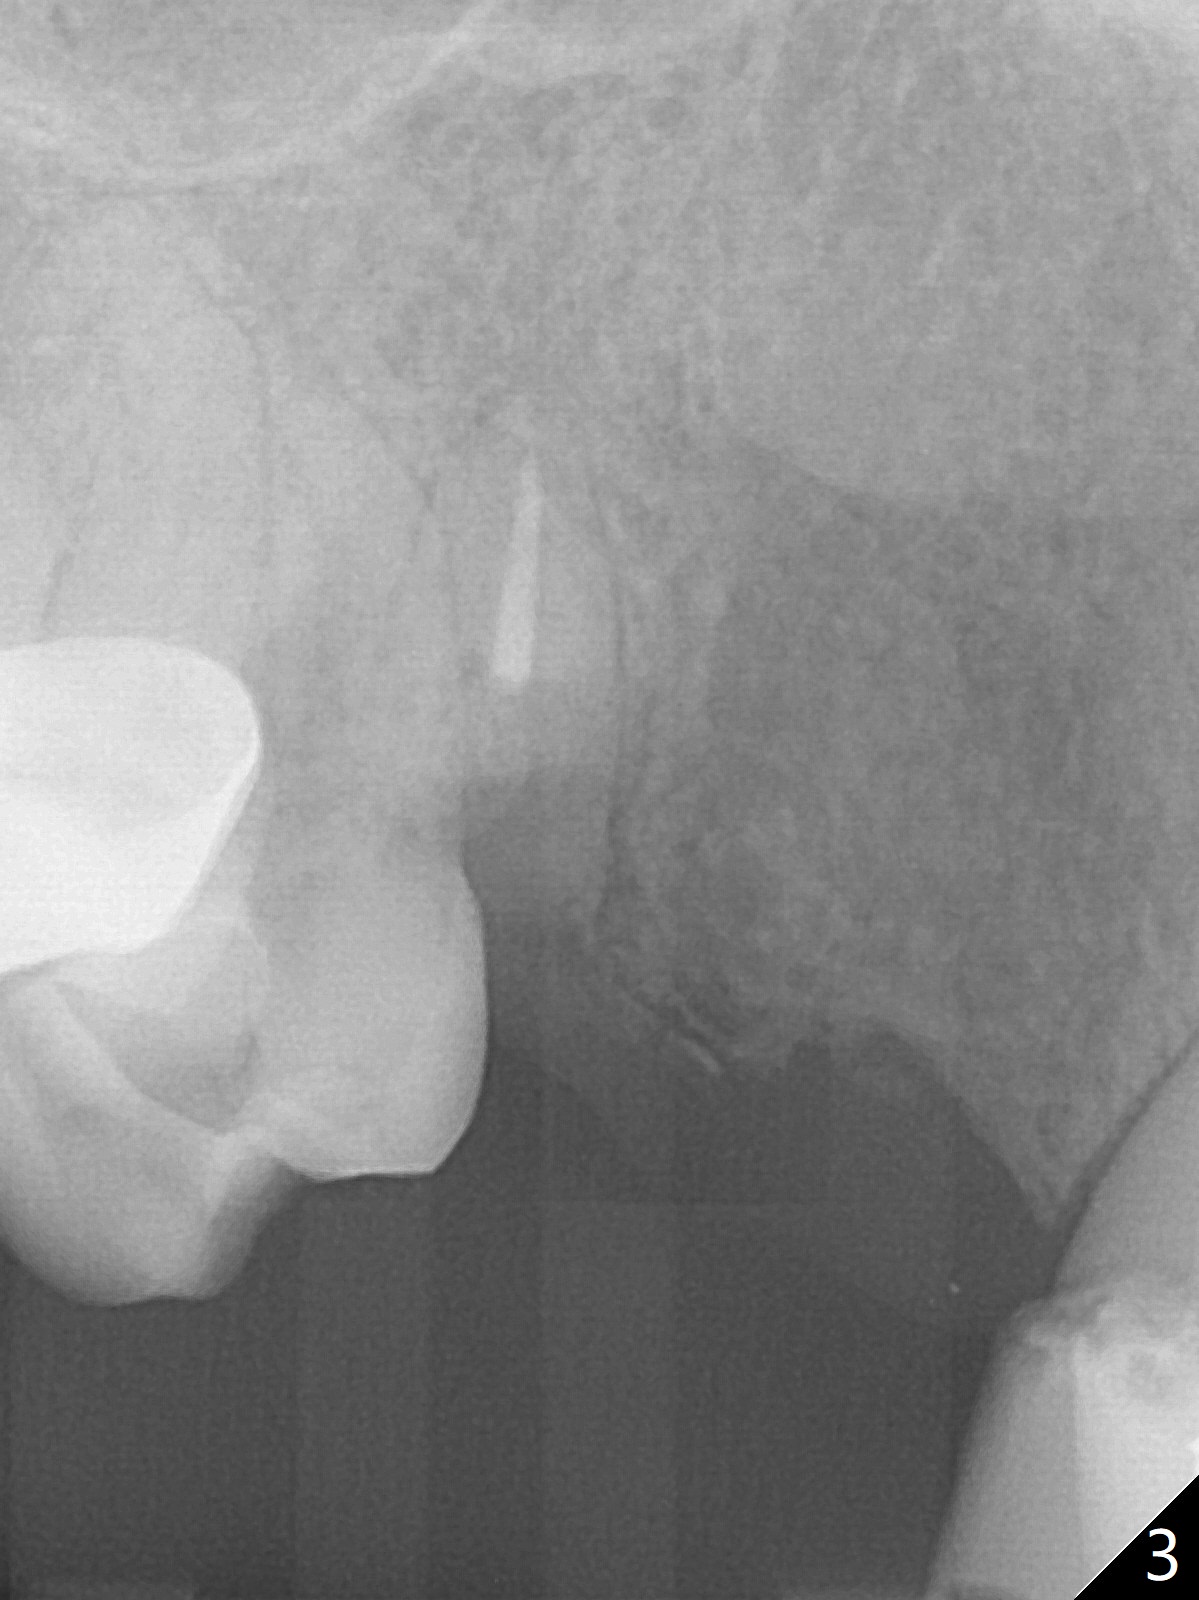

A 38-year-old skinny woman has several missing teeth (Fig.1). Recently a #6-7 cantilever FPD dislodged (Fig.2,3). The buccal plate at #6 must be thin. Socket shield should be indicated, particularly when extraction turns out to be difficult. A 4x13 mm IS implant is going to be inserted as distal as possible to avoid touching the apex of the tooth #5 (Fig.4,5). Since the ridge at #7 is narrow, a 1-piece implant will be placed (possible 2.5x14(2) mm, Fig.5). Take PA after the 1st drills. Take preop photos to show the residual root at #6 and the narrow ridge at #7.